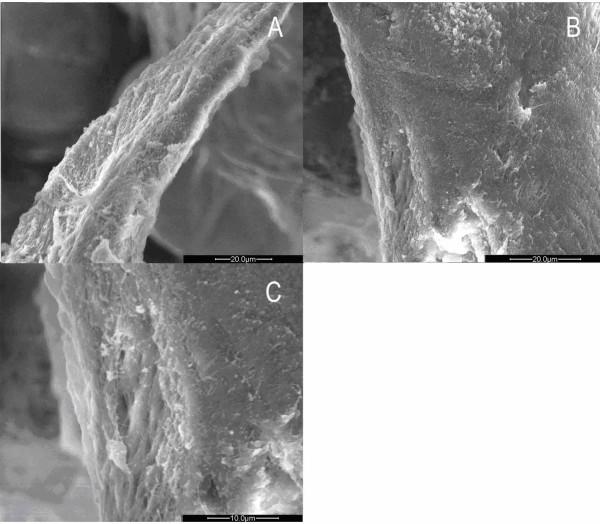

To compare the exact difference in bone tissue structure between osteoporosis and osteoarthritis, we observed the ultrastructure of trabecular bone from the femoral heads using scanning electron microscopy (SEM) and transmission electron microscopy (TEM). A total of 15 femoral head specimens from postmenopausal women were collected during the procedures of total or hemi hip replacement (OP, n = 8; OA, n = 7). The morphologic structure of the trabecular bone, collagen fibers, resorption lacuna and osteoblasts were observed.

Under SEM, osteoporotic trabeculae appeared to be thinning, tapering, breaking and perforating. A number of resorption lacunae of various shapes were seen on the surface of the trabeculum. The collagen fibers of lacuna were resorbed. On occasion, naked granular bone crystals could be found. In the OA group, the trabecular bone looked thick with integrated structure. Reticular and granular new bone could be found. The trabeculum was covered by well-arranged collagen fibers around the resorption lacuna. In the OP group, under TEM, marginal collagen fibers were observed to be aligned loosely with enlarged spaces. A few inactive osteoblasts and no inflammatory cells were seen. In the OA group, the collagen fibers inside the trabeculum were arranged in a dense manner with many active osteoblasts and inflammatory cells infiltrating the matrix.

在SEM下,骨质疏松的小梁骨显得变薄、变细、断裂和穿孔。在小梁骨表面可见许多各种形状的吸收陷窝。陷窝内的胶原纤维被吸收。偶尔可以发现裸露的颗粒状骨晶体。在OA组,小梁骨看起来厚实,结构完整。可以发现网状和颗粒状的新骨。在吸收陷窝周围,小梁骨被排列良好的胶原纤维覆盖。在OP组,在TEM下,观察到边缘胶原纤维排列松散,间隙增大。可见少数不活跃的成骨细胞,未见炎症细胞。在OA组,小梁骨内的胶原纤维排列密集,有许多活跃的成骨细胞和炎症细胞浸润基质。